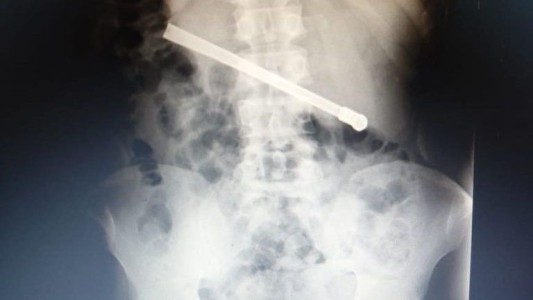

Médico explicó los riesgos de la peligrosa práctica de tragar objetos en prisión

Preso se tragó una bombilla para salir de la cárcel: habló la secretaria de Asuntos Penitenciarios

Interno condenado por abuso sexual fue operado tras ingerir una bombilla